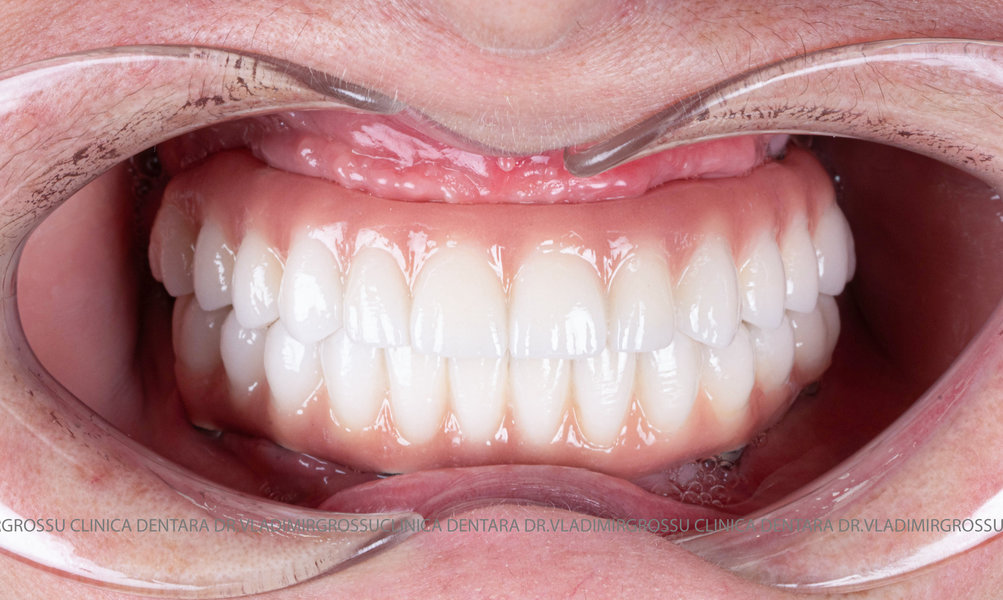

Caz 1

Caz 2